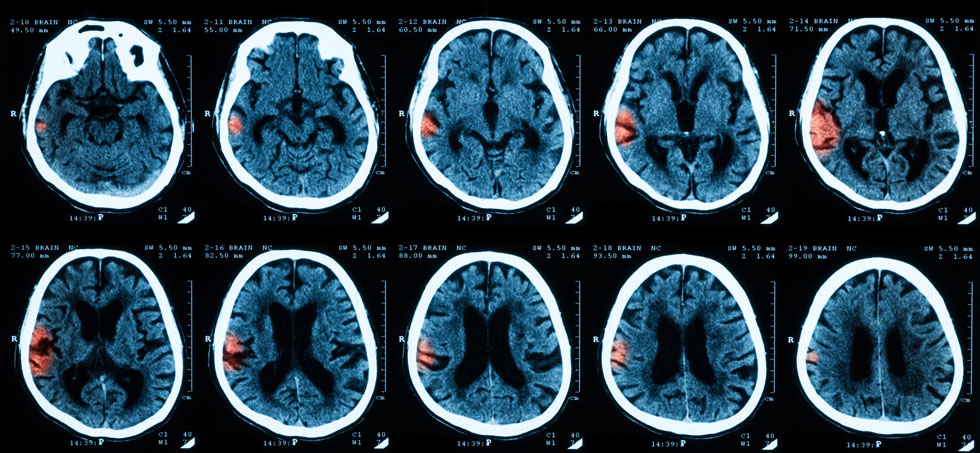

Whether asymptomatic intracranial hemorrhage (ICH) affects the clinical outcomes in patients with acute large vessel occlusion treated with mechanical thrombectomy (MT) remains unclear. This study aimed to address this uncertainty.

Asymptomatic ICH was defined as ICH without symptomatic ICH defined by the SITS-MOST criteria. A favorable outcome was defined as an mRS score ≤ 2 at 90 days after stroke onset.